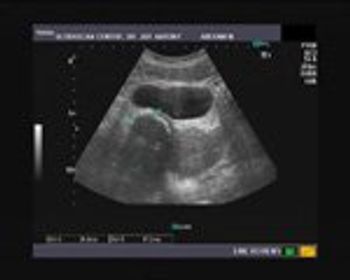

This was a female patient 32 years old, who had irregular menses. She was married for 5 years but unable to conceive.